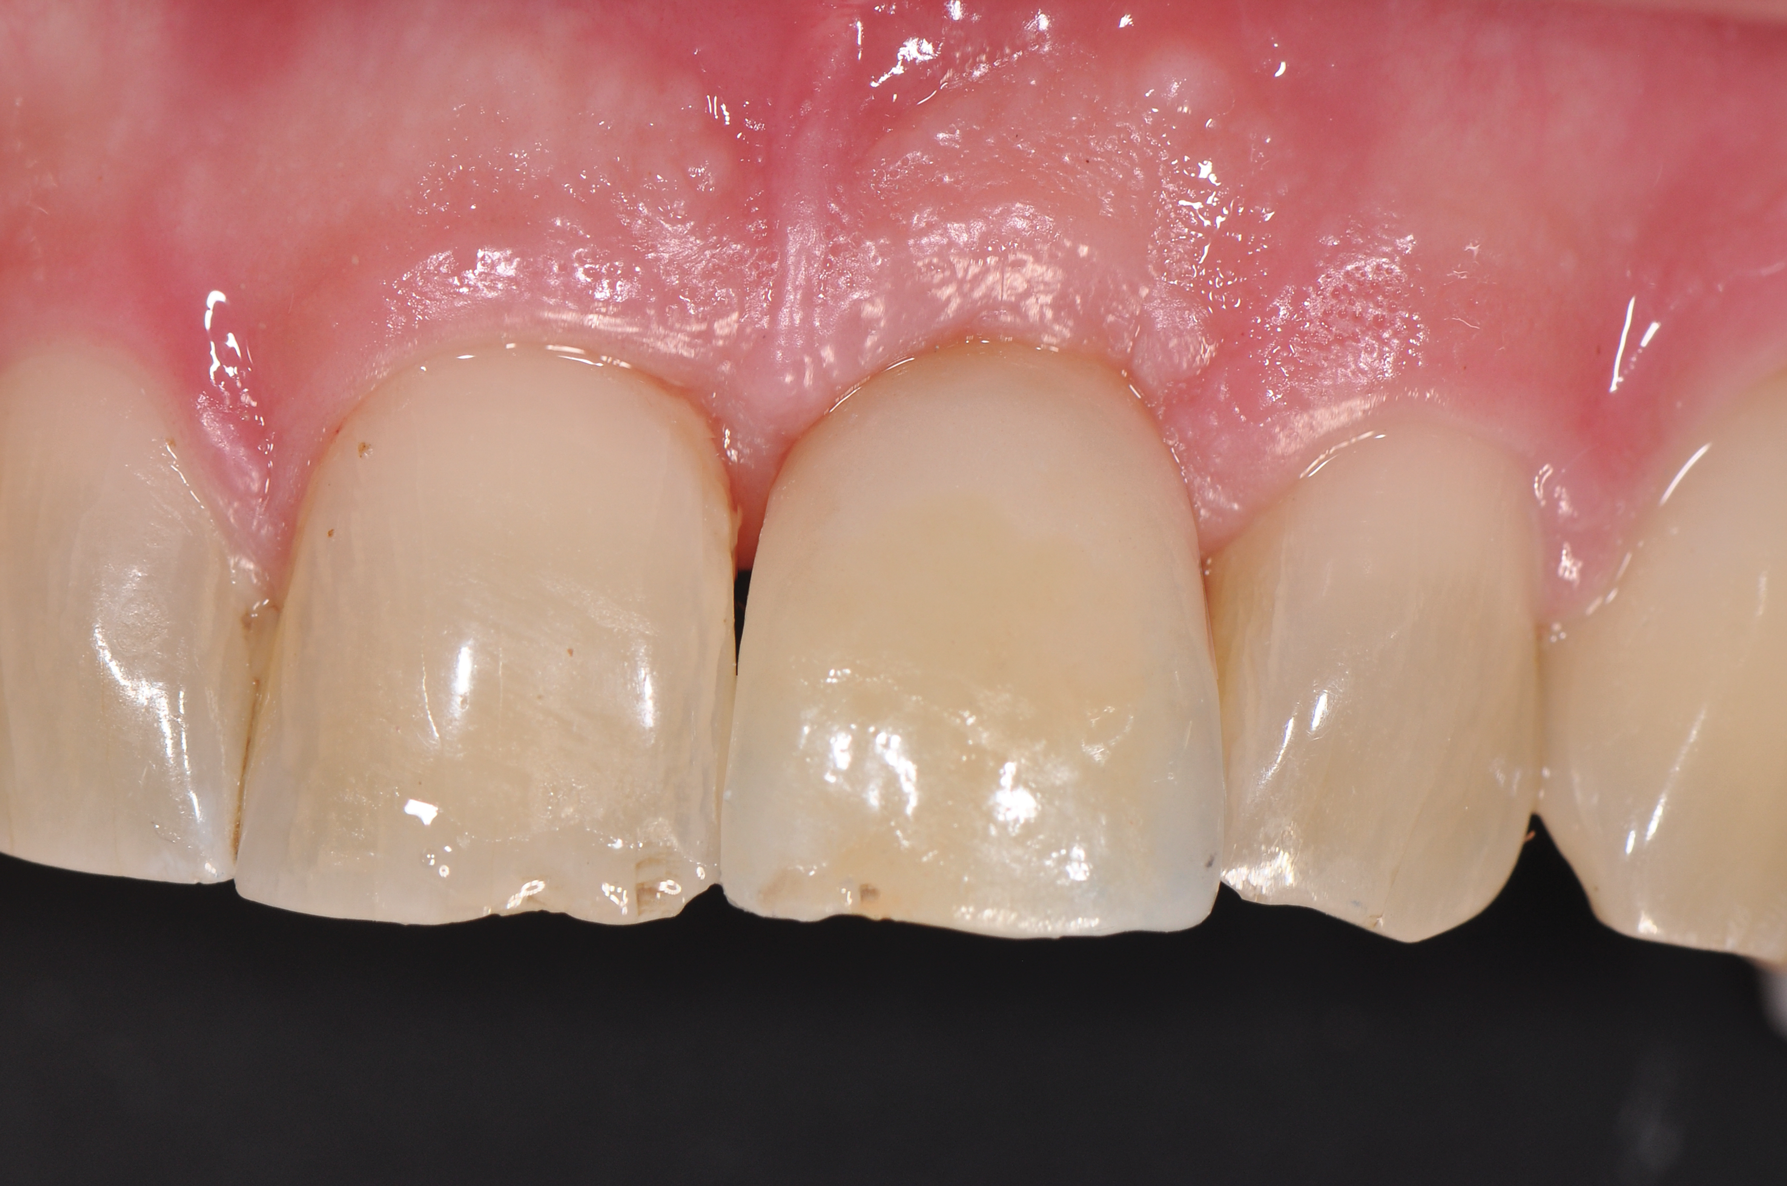

Fig 9. Healed implant site 12 weeks after surgery before re-entry.

Figure 9

Fig 10. Emergence profile was formed for 6 weeks with the use of a temporary restoration with a screw-retained PEEK abutment.

Figure 10